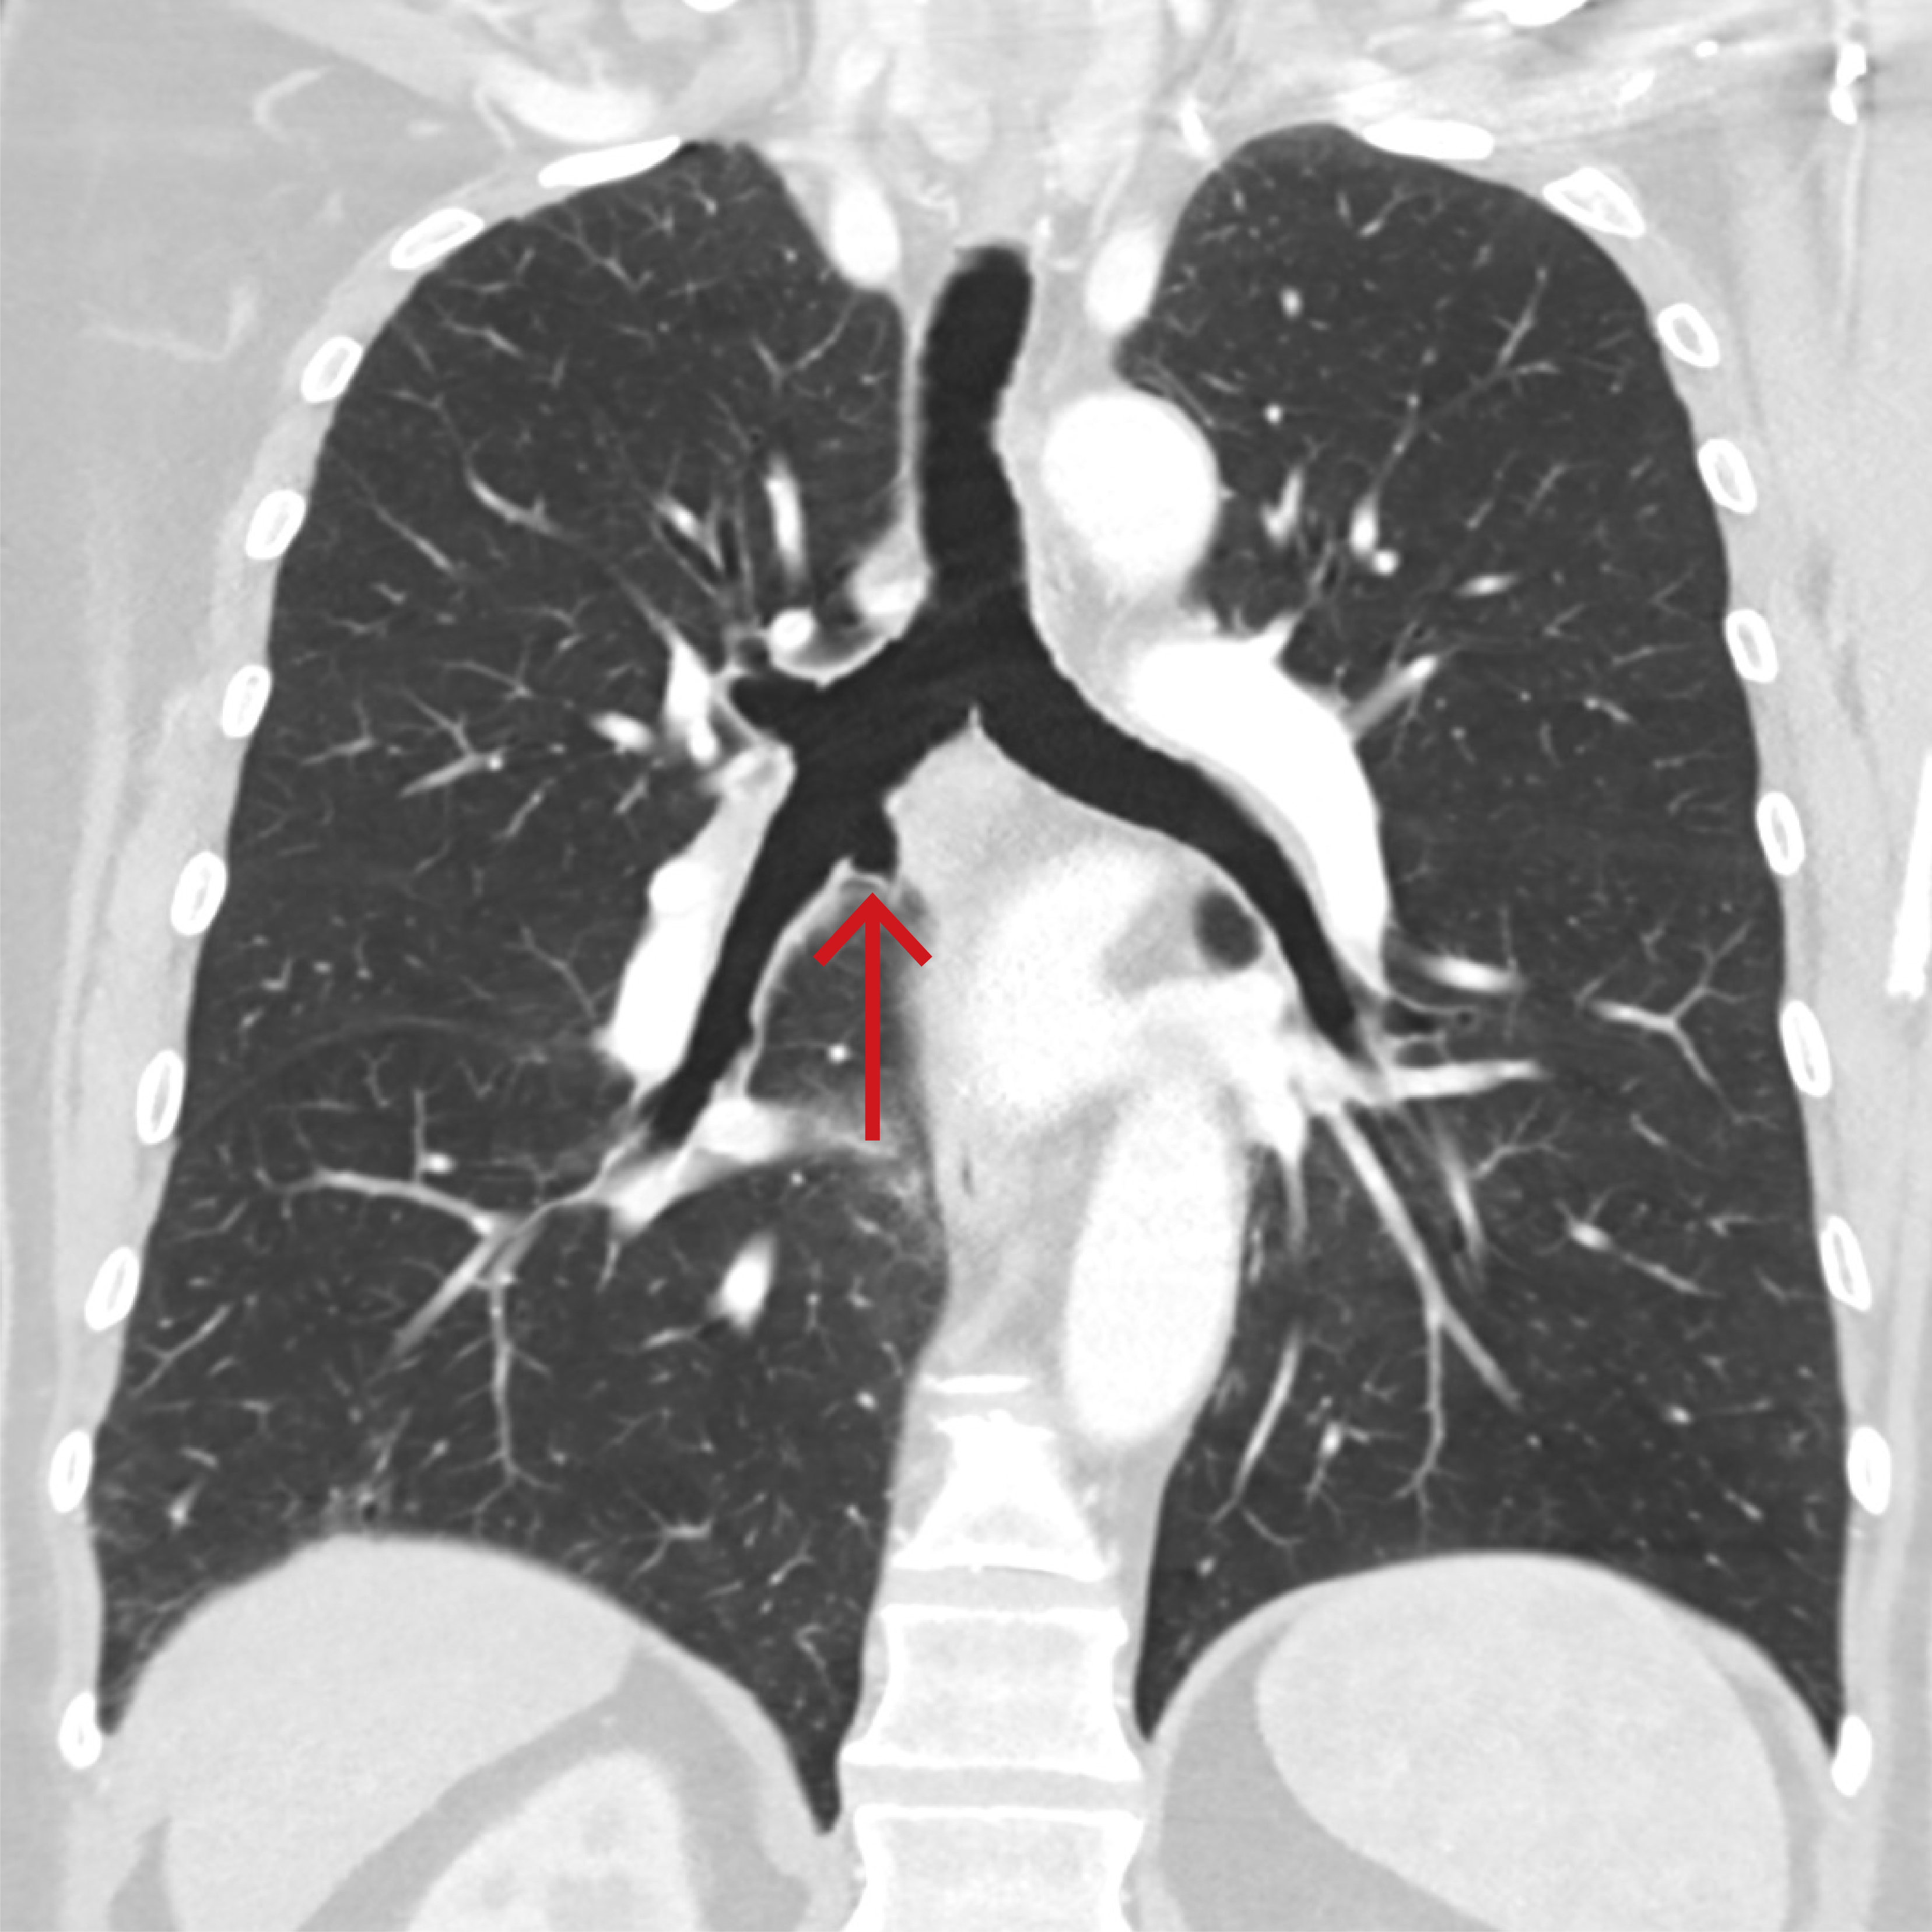

Rettelse Rettelse: Anatomisk variant i bronkialtreet Sigrid Anna Aalberg Vikjord, Even Hovig Fyllingen, Michael Krauss-Schilling Om forfatterne Se alle artikler Sigrid Anna Aalberg Vikjord Se alle artikler Even Hovig Fyllingen Se alle artikler Michael Krauss-Schilling Kommentert artikkel () sporsmal_grey_rgb Artikkel Tidsskr Nor Legeforen 2024; 144. doi: 10.4045/tidsskr.24.0383 I figuren skulle pilen være plassert her: (Rettet 20.12.2024) Relaterte artikler Anatomisk variant i bronkialtreet Kommentarer ( 0 ) Dette kommentarfeltet modereres, men kommentarer blir ikke redaksjonelt behandlet ut over å sikre at de følger retningslinjer for vårt kommentarfelt. Denne artikkelen ble publisert for mer enn 12 måneder siden, og vi har derfor stengt for nye kommentarer. Publisert: 20. desember 2024 Tidsskr Nor Legeforen 20. desember 2024 Vol. 144. doi: 10.4045/tidsskr.24.0680 Opphavsrett: ©️️ Tidsskriftet 2026 PlumX Publisert: 20. desember 2024 Tidsskr Nor Legeforen 2024 Vol. 144. doi: 10.4045/tidsskr.24.0680 Opphavsrett: ©️️ Tidsskriftet 2026 Plum Print visual indicator of research metrics PlumX Metrics PDF Får du ikke vist PDF-filen eller vil lagre filen, kan du høyreklikke på PDF-ikonet. Velg «Lagre mål/fil som..» og hent så opp PDF-filen i for eksempel Acrobat Reader. Skriv ut Anbefalte artikler